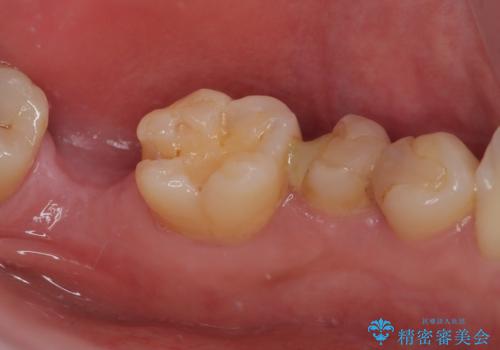

- 詰め物が外れかけているのでやり替えたいとのことで来院された患者様です。来院時に詰め物の不適合を認めたので歯髄診を行い歯髄の生活反応を確認できたので、フルジルコニアクラウン、セラミックインレー修復を行っていくことにしました。

拡大鏡視野下で、コンポジットレジン、虫歯の除去を行い、フルジルコニアクラウン、セラミックインレーに適した形に整えました。